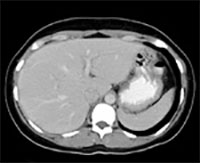

Abdominal imaging filmstrip

Abdominal Imaging

Our mission in the Abdominal Imaging section at the University of Colorado Anschutz Medical Campus is to provide exceptional Abdominal Imaging services including radiography, fluoroscopy, ultrasound, computed tomography (CT), and magnetic resonance imaging (MRI). Our section focuses on all aspects of Abdominal Imaging, with primary areas of emphasis including, but not limited to, oncology, transplant and critical care imaging.